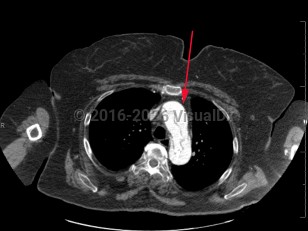

Chest pain, Dyspnea, 50-59 year old Female

Aortic dissectionAortic dissection